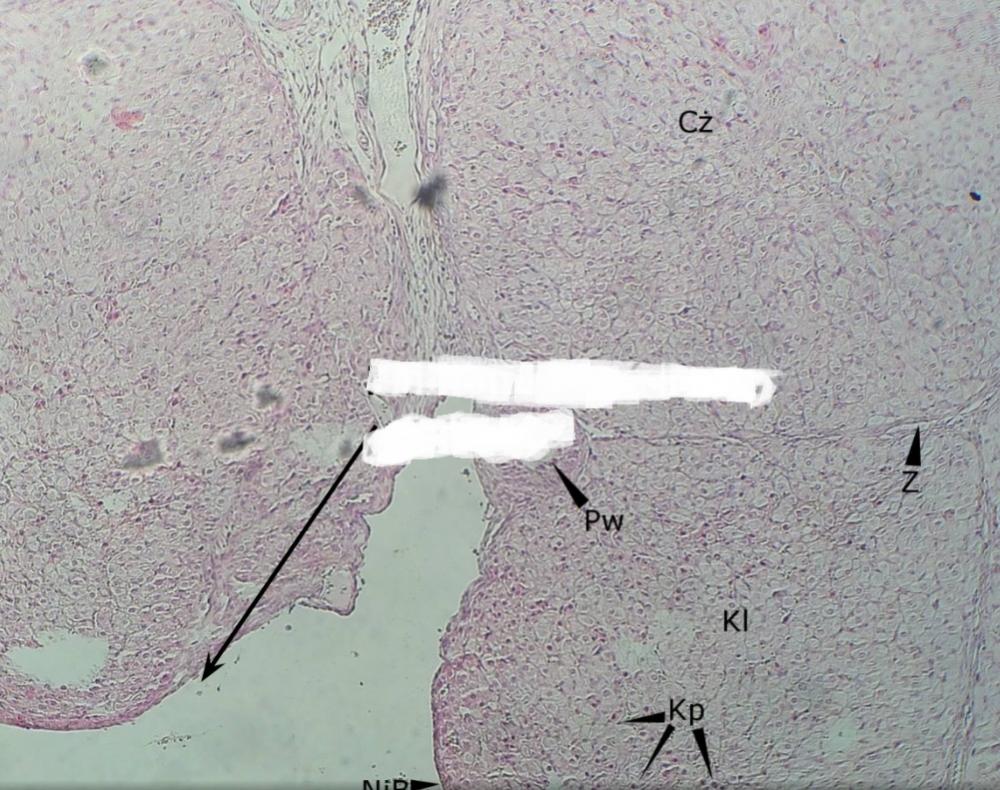

Pytanie 432

taśma okrężnicy (jelito grube)

Pytanie 433

nabłonek jednowarstwowy walcowaty (wyrostek robaczkowy)